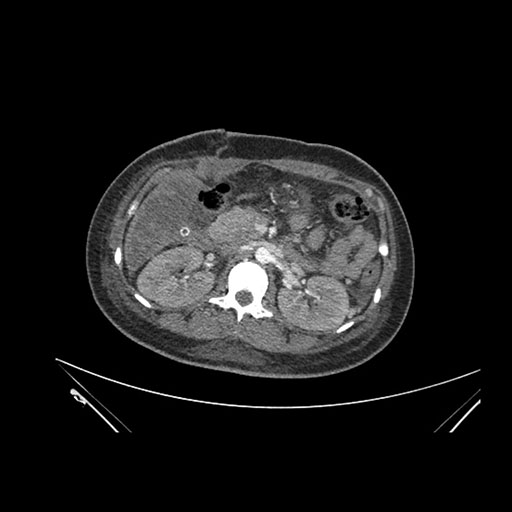

Axial Arterial

Axial Venous